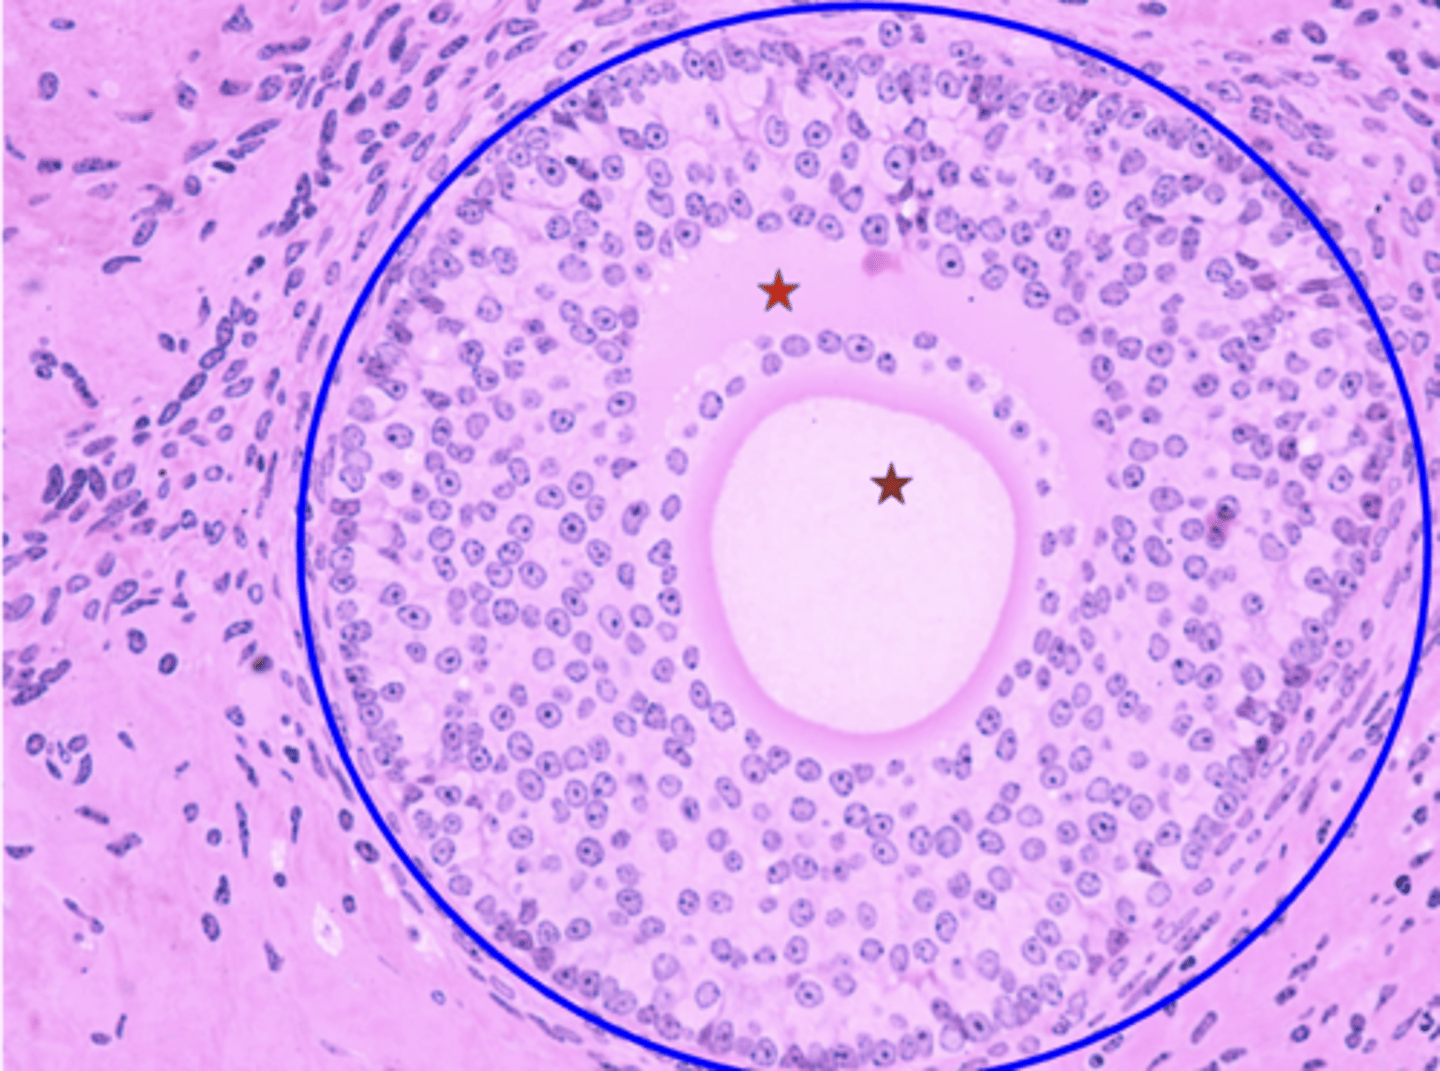

Germinal epithelium

What is the black arrow?

Tunica albuginea

What is the red arrow?

Primordial follicles

What is the green arrow?

Multilaminar primary follicle

What is the blue circle?

Primary oocyte

What is the red star?

Simple cuboidal epithelium

Tissue type of germinal epithelium?

Fibrous layer of connective tissue

Tissue type tunica albuginea?